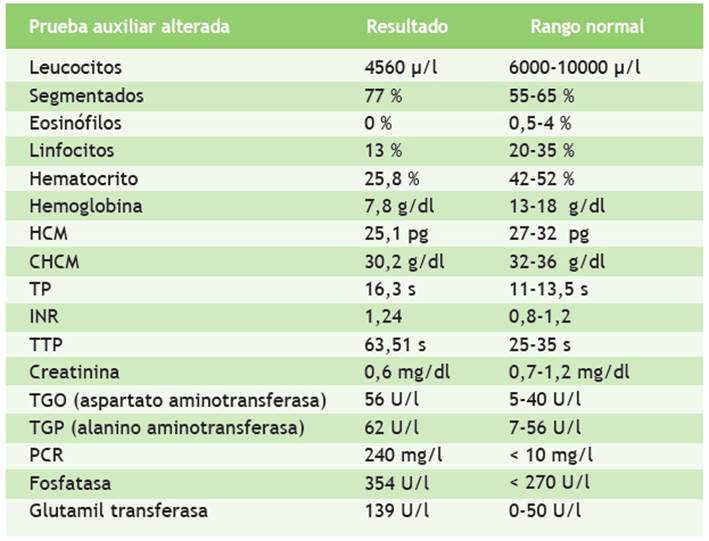

En la Tabla 1 se muestran los exámenes de laboratorio que se realizaron durante la hospitalización del paciente: baciloscopia en esputo con resultado negativo, baciloscopia en orina con resultado 5 BAAR y baciloscopia en heces que resultó positiva (+), ecografía torácica con reporte de líquido libre en ambos hemitórax, un volumen de 400 ml en el hemitórax izquierdo y 150 ml en el derecho; radiografía de tórax que muestra derrame pleural bilateral con predominio izquierdo (Figura 1); ecografía abdominal con hallazgos de esplenomegalia y nódulos hipoecogénicos (Figura 2); test de adenosina deaminasa en líquido pleural con valor 33. Los resultados de carga viral para VIH fueron 181 000 copias/ml y CD4: 63.

Figura 1 La radiografía de tórax anteroposterior muestra radiopacidad homogénea en tercio inferior del campo pulmonar izquierdo (flecha amarilla), que obtura seno costofrénico, con signo de menisco (líneas punteadas rojas). Seno costofrénico derecho libre y elementos óseos y partes blandas con características habituales